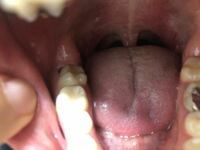

親知らずのせいで歯並びが悪くなっている気がする 治療期間 1日 治療費用 ¥10,000(ct代込) 治療内容 痛みなどの症状はなく、歯肉の中に完全に埋まっている歯でしたが親知らずのせいで歯並びが悪くなっている気がするとのことで抜歯を希望されました。親知らずの抜歯は、 外科的技術 が必要となります。 当院では完全に埋まっている、横向きに生えているなど、難しいとされる抜歯も行なっております。 しかし感染による炎症がある場合は、抗菌薬によって症状を軽くしてからでなくては抜くことが出来 05年6月23日 2118 私もつい先日歯医者でレントゲンを撮った時に親知らずが埋まってるということに初めて気が付きました。 というか、先生に

埋まってる親知らず 虫歯- その際、左上・親知らず(うっすらと歯茎から見え始めている状態)に関して相談したところ、左上・左下ともに次回抜歯しましょうという話になりました。 左下は完全に 歯肉 に埋まっている状態で、最初にかかった歯科でも一切触れられなかったため 完全に埋まっている 親知らずが横向きでそのまま完全に埋まっている場合もあります。 完全に埋まっているために虫歯などのリスクは低めですが、 歯が生えてこようとする力が横向きに加わり一つ前の歯を押してしまい歯並びに悪影響がある場合もあり

親知らずに痛みや腫れのある方。 症状はないけど抜いた方がいいのか悩んでおられる方。 親知らずでお悩みの患者さんは大勢いらっしゃると思います。 このページでは親知らず抜歯に関する様々な疑問にお答えしています。 お困りの際は是非一度ご相談ください。 親知らず、4本ともあるよー\(^0^)/ 絶望が、脳内をよぎりました。。。 必死で、埋まっている親知らずをについて医師に聞いてみる。 自分 「これ4本とも抜かないといけないんですかね??」 するとどっこい。 医師 「いや、他3本は抜かなくて良いと思うよ。 こんな時は抜いた方が良い 親知らずが歯茎から半分だけ顔を出している場合は 抜いた方が良い です。 なぜなら汚れがたまりやすく、 においや虫歯、痛みが出やすいからです 。 また歯茎に完全に埋まっていても、違和感を感じる場合も抜いた方が良い